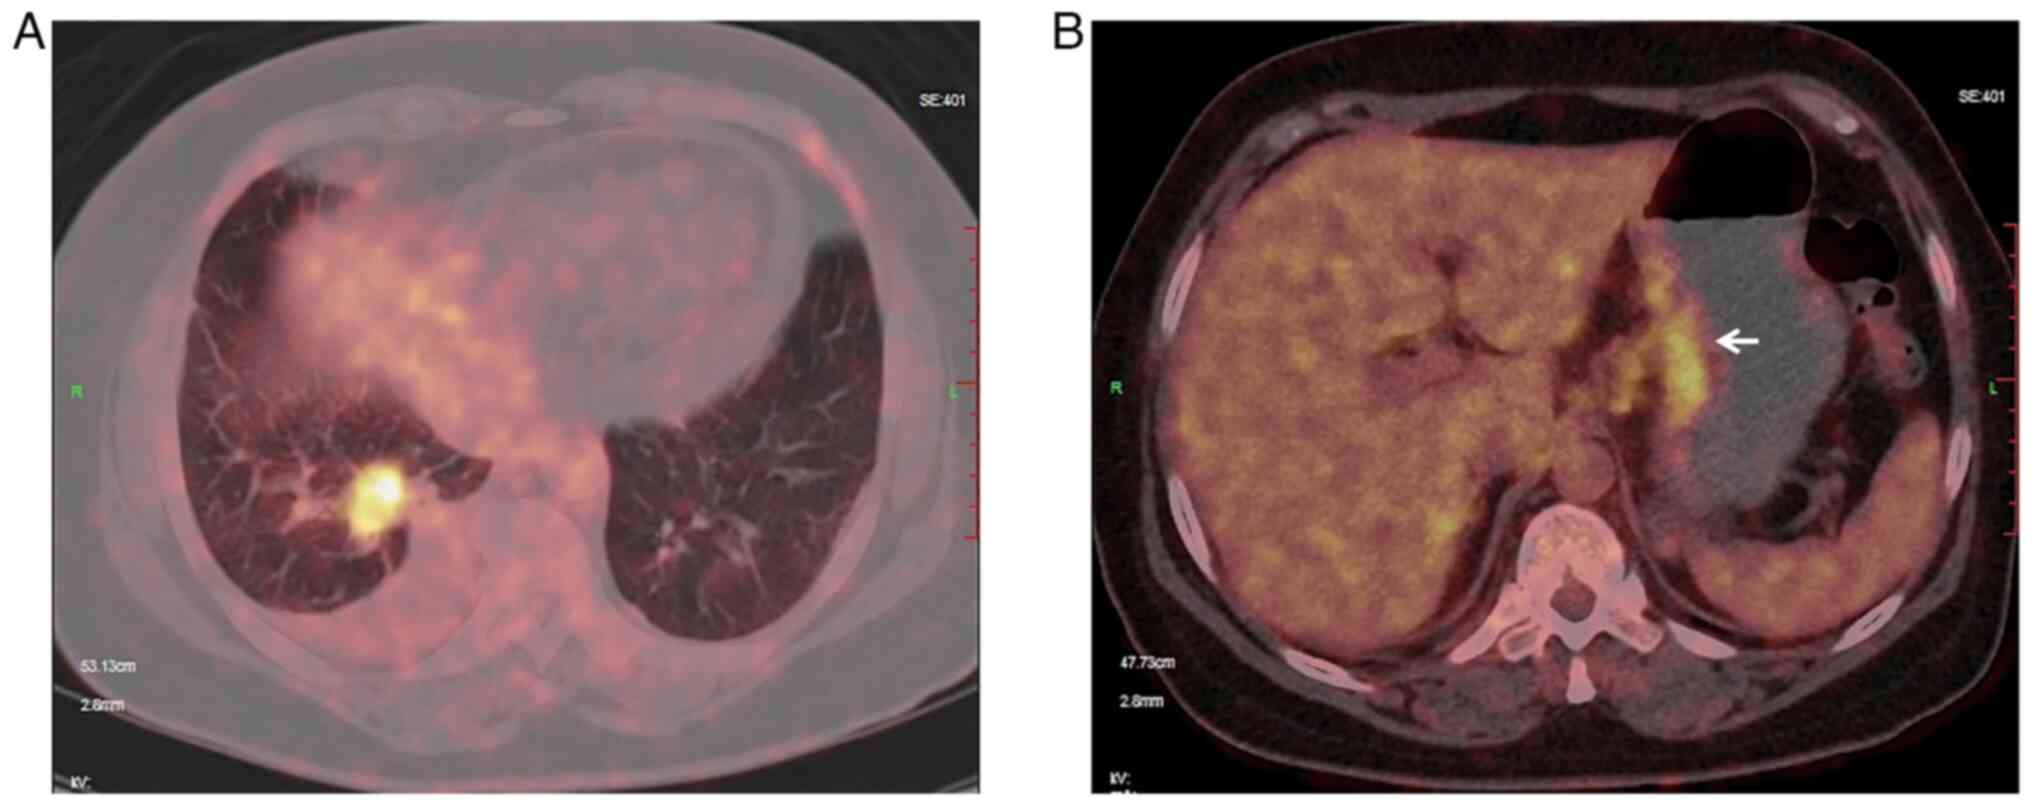

Endoscopic manifestations and treatment outcomes of asymptomatic gastric metastases from primary lung adenocarcinoma: Report of two cases

Metastatic spread of lung adenocarcinoma to the stomach is rare and most gastric metastases are discovered at the advanced stage due to certain symptoms. The present study reported two cases of asymptomatic gastric metastases from lung adenocarcinoma presenting as diminutive nodules or erosion endoscopically. The manifestations were also visualized under magnifying endoscopy with blue laser imaging (BLI‑ME), the two cases share certain common characteristics under BLI‑ME, such as an obviously widened intervening part and extended subepithelial capillary network, which indicated that lesions developed beneath the superficial epithelium. Target biopsy and further immunohistochemical staining confirmed that the gastric lesions were metastatic from primary lung cancer. None of the two patients were candidates for surgery due to multiple distant metastases, but the gastric metastases regressed to scars after systemic anticancer therapy. These two cases were presented in order to improve the current understanding of the endoscopic manifestations of early gastric metastases from lung cancer, and the outcomes may demonstrate that systemic treatment is effective for eliminating early gastric metastatic lesions.

Figure 1

Figure 2

Figure 3

Figure 4